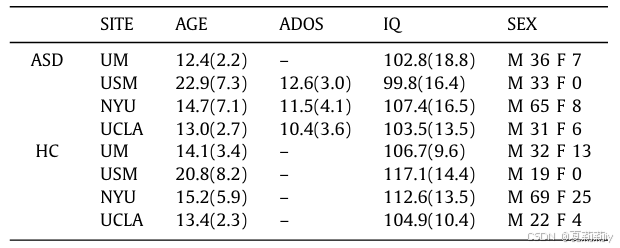

①Sites chosen: the largest four, UM1、NYU、USM、UCLA1 with 106, 175, 72, 71. Eliminating incomplete data samples, left 88, 167, 52, 63 each

④Sample statistics:

⑤Demographic data: